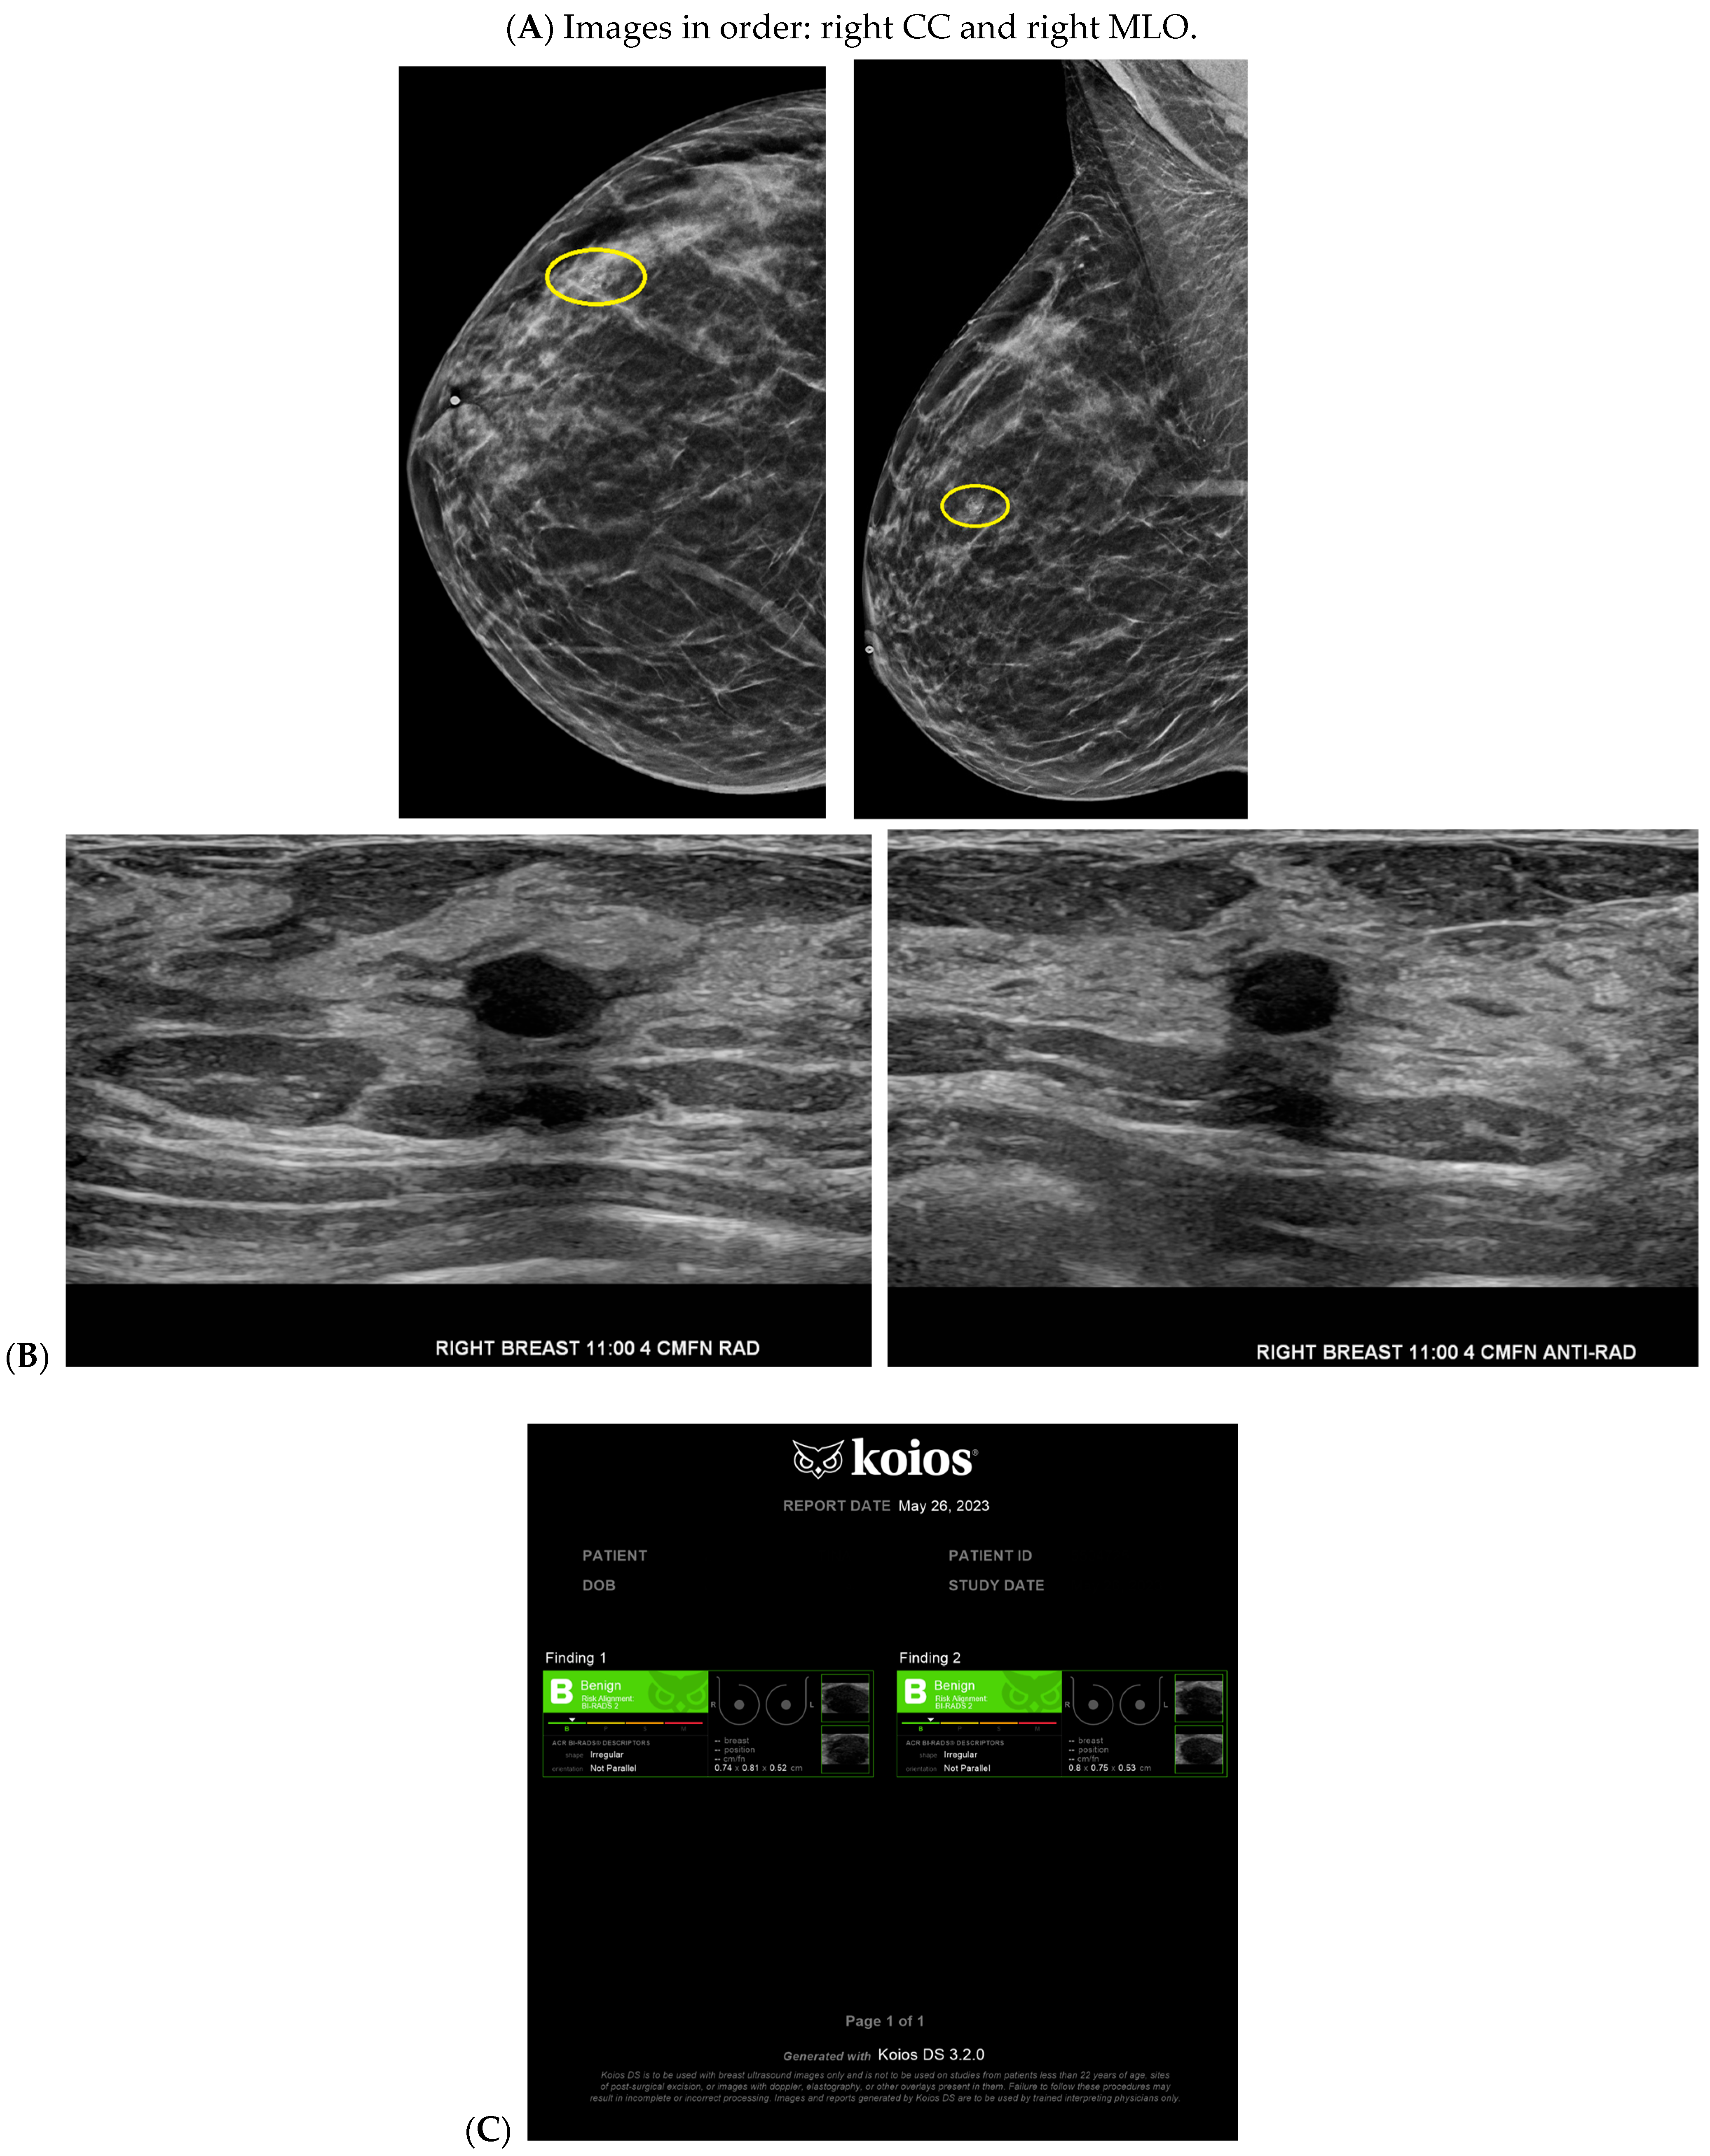

Figure 4.

A benign finding appropriately classified as benign by artificial intelligence (AI): The patient initially presented for a bilateral screening mammogram and a bilateral screening breast ultrasound. A mammogram revealed benign dystrophic calcifications in the upper outer quadrant of the right breast (A). Correlating with findings on the mammogram, ultrasound revealed a complicated cyst showing posterior acoustic shadowing consistent with fat necrosis (B). The AI program Koios recognized this mass as “Benign” (C). Images obtained from the Icahn School of Medicine at Mount Sinai.